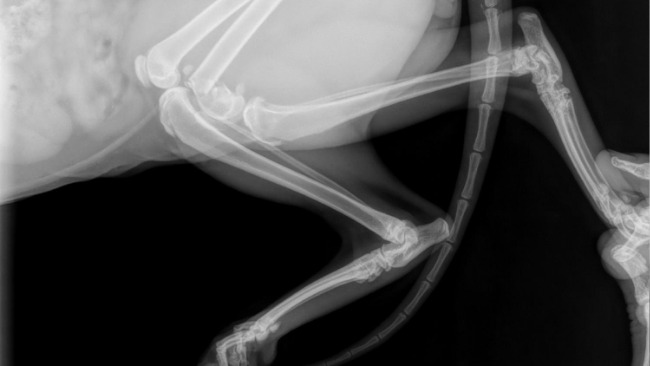

Po przybyciu do kliniki weterynaryjnej, lekarze przeprowadzili szczegółowe badania, które ujawniły uraz – złamanie przynasady kości udowej lewej.

W zaleceniach natychmiastowe wykonanie zabiegu ortopedycznego (dwa złamania).